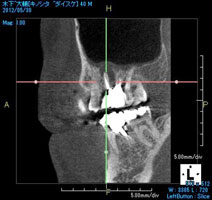

そこで根の形態が複雑だと判断した場合にはCT撮影を行い根の形態を3次元的に把握して治療を行っています(図2)。

図2